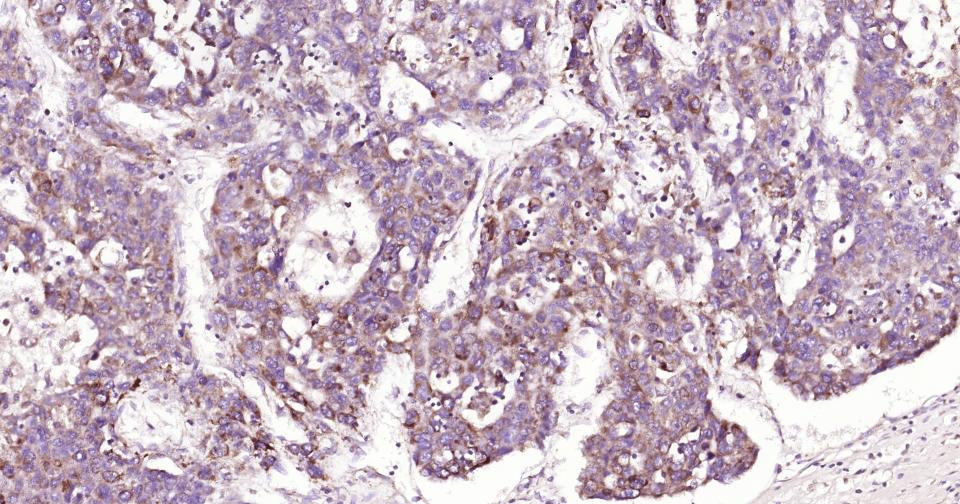

Paraformaldehyde-fixed, paraffin embedded Human Liver Cancer; Antigen retrieval by boiling in sodium citrate buffer (pH6.0) for 15 min; Antibody incubation with AIF Monoclonal Antibody, Unconjugated(bsm-34316R) at 1:200 overnight at 4°C, followed by conjugation to the SP Kit(Rabbit, SP-0023) and DAB (C-0010) staining.